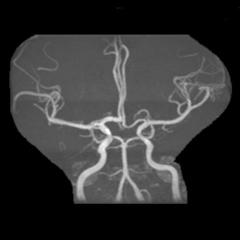

病例24:双侧大脑中动脉M1段动脉瘤合并基底动脉开窗畸形